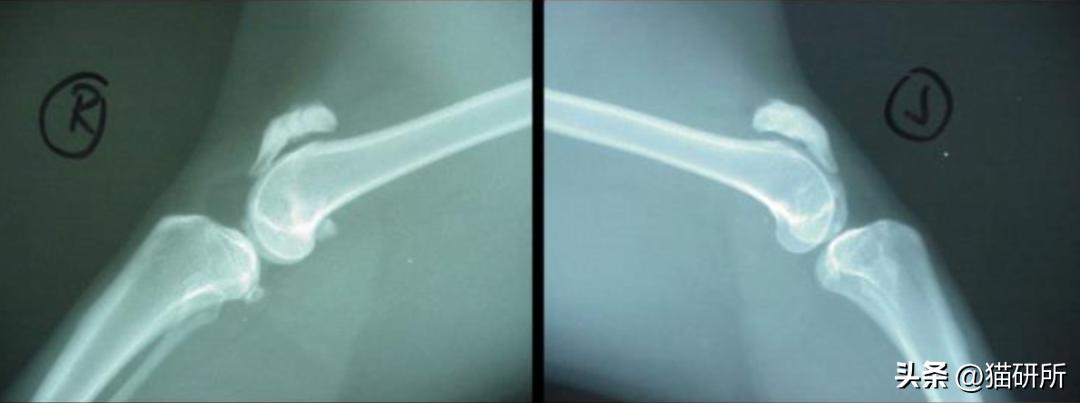

顺着这个思路,研究人员搜集了2005~2018年间,共191例猫咪髌骨骨折病例。

在回顾研究中发现:

· 约一半(92只)的猫咪都存在牙齿问题 ,包括 乳牙滞留 和 恒牙无法正常萌出 等。

· 出现跛行和髌骨问题的猫咪73%都是双侧髌骨骨折,且40.8%的猫咪除了髌骨骨折,髋臼、胫骨、坐骨、髂骨等地方也出现了1~6次骨折。

· 第一次髌骨骨折通常出现在1-3岁,并在3个月内另一侧髌骨接着骨折;

· 骨折可能会反复多次发生;

· 与外伤不同,PADS的骨折基本都是单纯的横向骨折。

后续容易发生骨折的部位

a)骨盆;b)胫骨;c)肱骨;d)跟骨